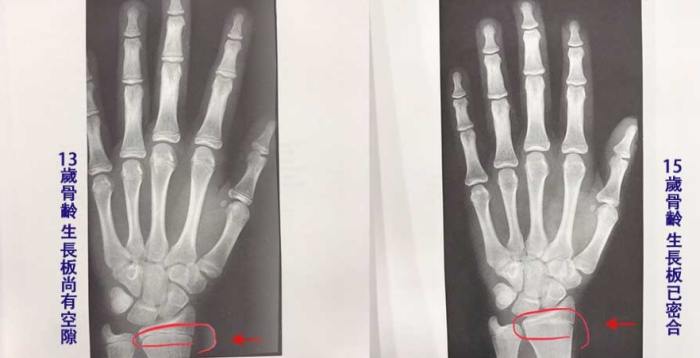

先來點基礎知識。生長板(Growth Plate)其實是長骨兩端的軟骨組織,它是我們身高增長的核心引擎。這東西就像個神奇的工廠,不斷生產新的骨細胞,讓我們從小豆丁慢慢抽高。

但問題是,這個工廠有營業時間限制。一般來說,女生在14-16歲、男生在16-18歲左右,生長板就會開始閉合。閉合後,骨頭就停止縱向生長,這也是為什麼很多人覺得青春期後就不可能再長高。

不過這裡有個常見誤區:生長板閉合不是瞬間完成的,而是個漸進過程。這就給了我們一些操作空間,關鍵是要抓住閉合前的最後機會,或者利用其他方式刺激殘餘的生長潛力。